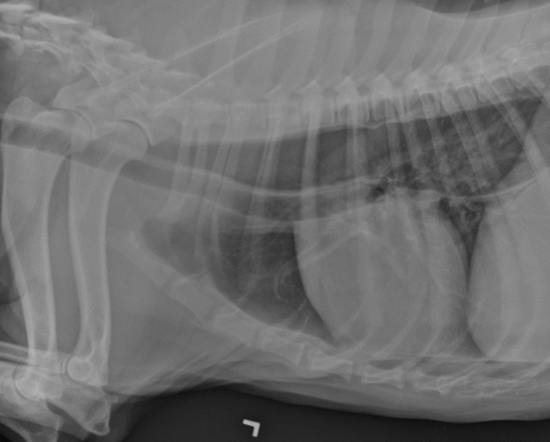

how are hiatal hernias diagnosed?

may manifest intermittently

-thoracic radiographs: caudodorsal, gas-filled intrathoracic soft-tissue opacity

-contrast videofluoroscopy swallow study (normal does not rule out a hiatal hernia)